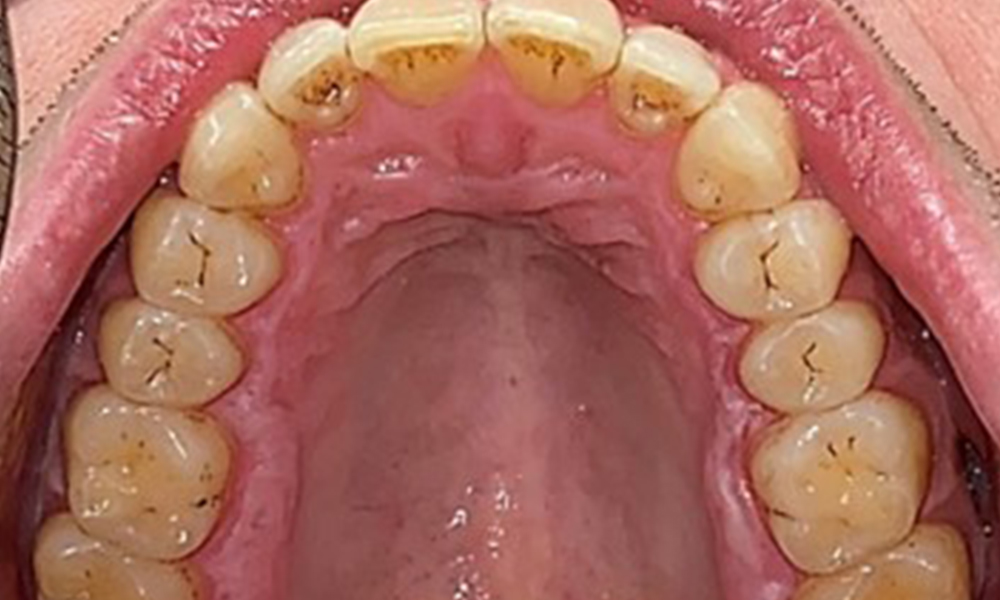

Extraoral and intraoral findings

There were no pathological extraoral findings. During intraoral examination, inspection of the frontal view revealed brownish discolouration near the keratinised gingiva and at the transition to the moveable mucosa (Fig. 2), which could be attributed to nicotine consumption. Whitish mucosal lesions were observed on the palate, particularly near the maxillary molar palatal surfaces, indicating increased keratinisation and can also be attributed to nicotine consumption. The tongue was covered with a removable white and brownish coating.

Occlusal view of the maxilla, © Dr R. Krapf

Fig. 3: Occlusal view of the maxilla, © Dr R. Krapf